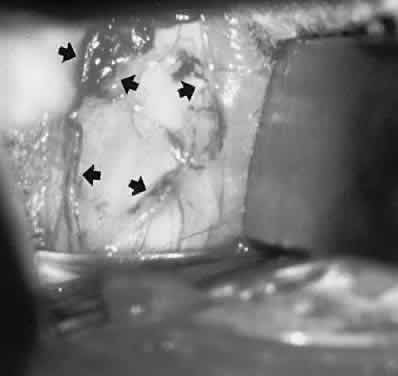

Abnormalities of the conjunctiva may serve as clues to orbital diagnosis. In general, edema (chemosis) is too nonspecific a finding to be very helpful, being common in Graves' disease, inflammatory pseudotumor, and arteriovenous fistulas. Any retrobulbar mass may produce chronic or intermittent chemosis, presumably by interfering with venous drainage in the orbit. In Graves' ophthalmopathy, the vessels overlying the insertions of especially the medial and lateral recti muscles are commonly enlarged, and indeed the muscle insertions themselves may be visibly hypertrophied (Fig. 5). These two conjunctival signs are exceedingly useful in identifying Graves' orbitopathy and should be sought in cases of unexplained proptosis and/or diplopia. Also, engorgement of orbital vessels may be reflected as hypervascularity of conjunctival and scleral vessels, which take on a more-or-less specific pattern in the presence of arteriovenous fistula (see Volume 2, Chapter 17, Fig. 14).

Fig. 5. Conjunctival signs of Graves' congestive orbitopathy. A. Characteristic fleshy hypertrophy of insertion of right lateral rectus (large arrows). Note localized chemosis of left caruncle (small arrow). B. Hypertrophy of insertion of medial rectus with hypervascularity of the vessels overlying the horizontal recti insertions (arrows).